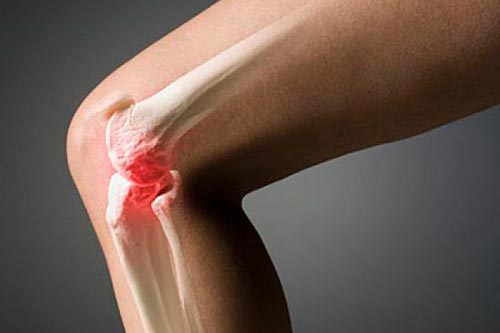

Остеоартроз(гонартроз) –заболевание коленного сустава, по мере развития которого хрящи разрушаются, а сустав теряет функциональность. На первых этапах гонартроза правого или левого колена нарушения происходят на уровне молекул. После приходит очередь гиалинового хряща. Он становится тонким и покрывается трещинками. Далее хрящ полностью исчезает, оставляя кость обнаженной.

Что такое артроз коленного сустава, вы можете узнать на любых профилактических беседах с врачом. При артрозе коленного сустава на кости появляется уплотнение, из которого со временем возникают шипы.

Деформирующий гонартроз проявляется и во внешних изменениях. При внешнем осмотре видна деформация сустава, искривление голени, очертания костей. К тому сложно разгибать и сгибать ногу.